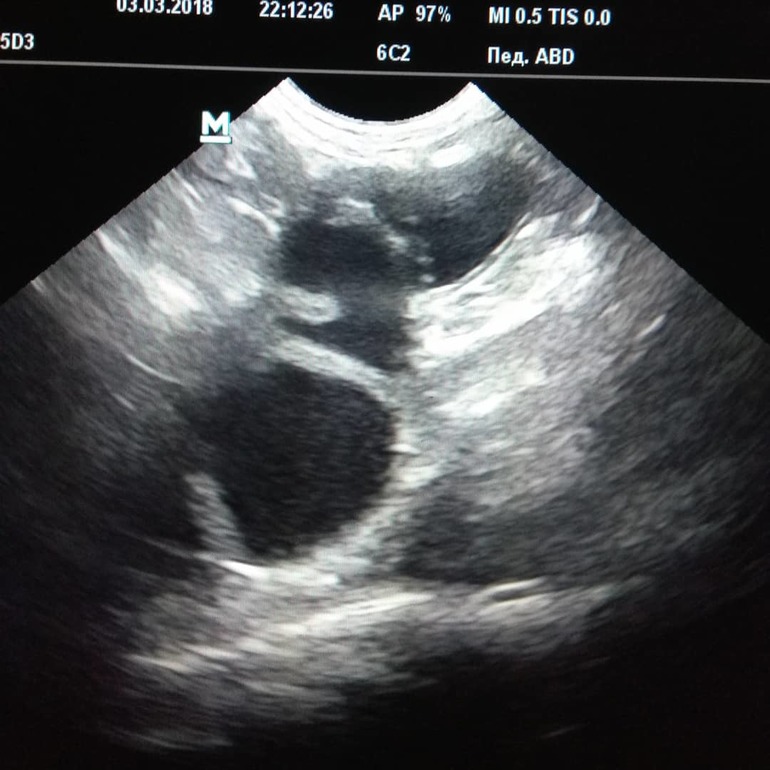

И тадааам

Это правый рог с жидкостью, как потом выяснилось с зелёным гноем с примесью крови. Второй рог я искала упорно, но как оказалось, он порвался из за перерастяжения, и весь гноюшник вытек в брюшную. Это все повело за собой воспаление брюшины и сальника. Собачке 6 лет, ни разу не вязалась, исправно текла и ходила с ложняками раз в год исправно. Сейчас она уже неделю лежит в интенсивке, ее лейкоциты равны рублевому счету сбербанка, не ест, не пьет. Ей повезло, что был хороший хирург в смене и то что хозяева , осознав все, отдали сразу на стол свое животное.

Пысы на фото рог матки, расширенный до 5см при норме до 1см при условии отсутствия в нем полости и жидкости